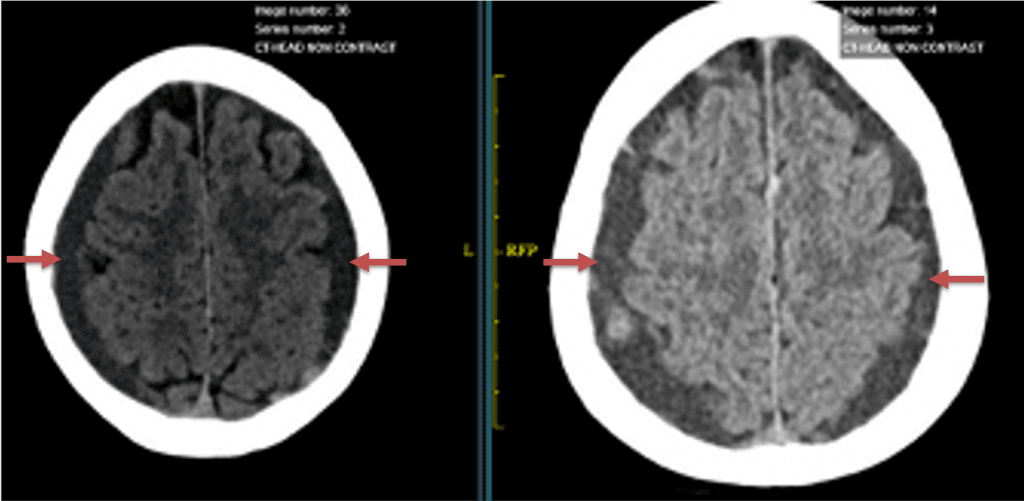

Clinically, the patient improved over the few weeks with the occasional transient twinge of a headache, but resolution of dizziness. Follow-up CT at 10 weeks demonstrated complete resolution of the bilateral subdural hematomas with our patient completely asymptomatic and back to all of her activities of daily living. Considering her history of thrombocytopenia and CLL, we will continue to monitor her into the future and are excited about her progress and recovery. (Figure 4. A and B)

Figure 4. A and B) – 10 weeks following embolization demonstrates complete resolution of bilateral collections both acute and chronic.